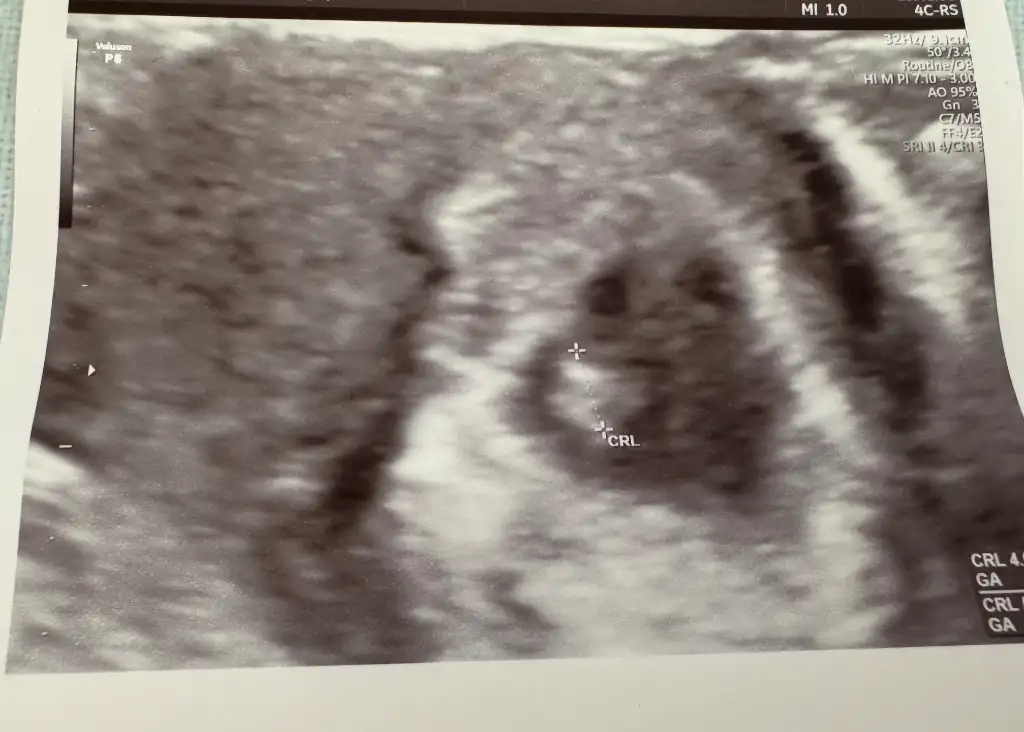

9 haftalık gebelik cinsiyet tahmini yapabilir misiniz kızlar bugün 11 haftalık 💕